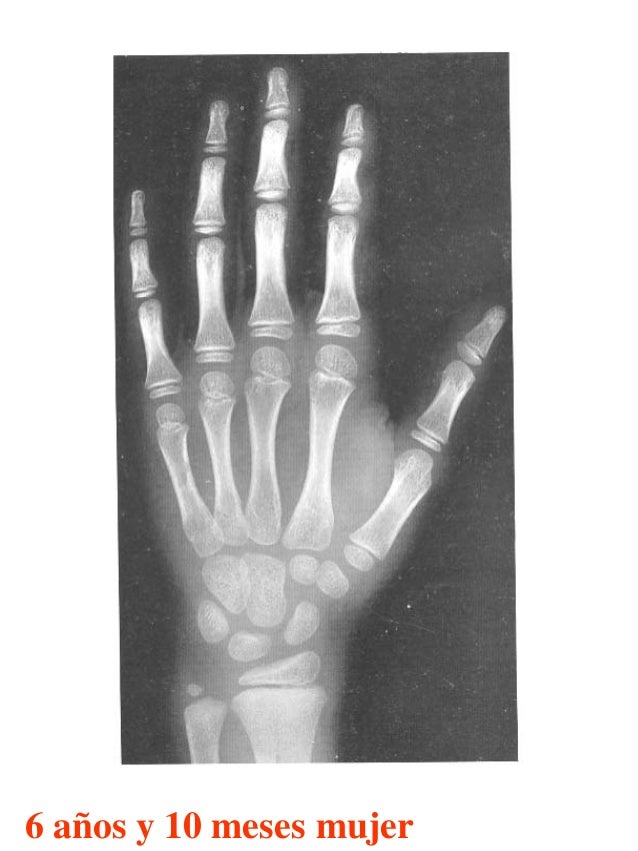

Figura 2 Imágenes de radiografías de mano y muñeca izquierda del

Figura 2 Imágenes de radiografías de mano y muñeca izquierda del Tablas De Greulich Y Pyle Edad Osea The greulich and pyle atlas is used to estimate the age of children and adolescents. El método de greulich y pyle(1) es un método simple de valoración de la edad ósea en pacientes pediátricos. El diagnóstico y la clasificación se basan en el examen físico, el análisis del crecimiento, la maduración ósea, la ecografía de útero y gónadas, y los. Tablas De Greulich Y Pyle Edad Osea.